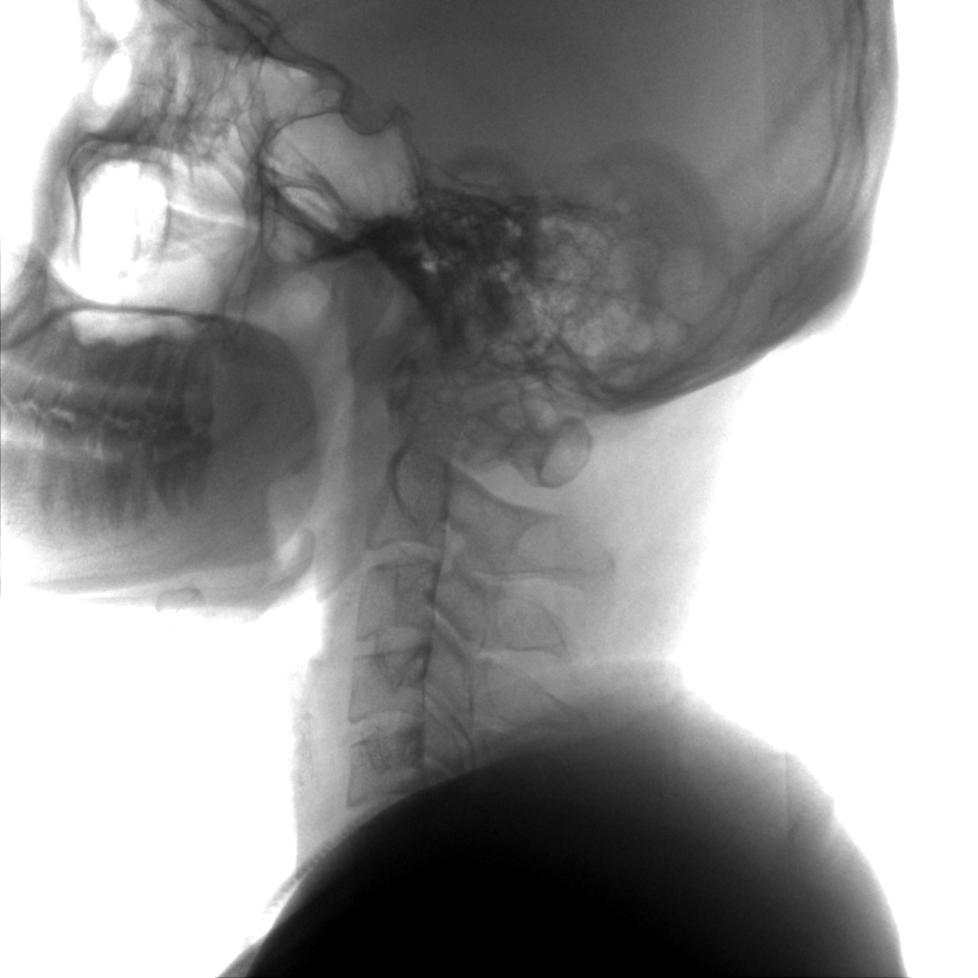

提供更大的術(shù)中三維成像視野,采集更多圖像信息,可一次拍全全段頸椎、全段腰椎、七節胸椎、雙側骶髂關(guān)節、股骨頭及單側盆骨。